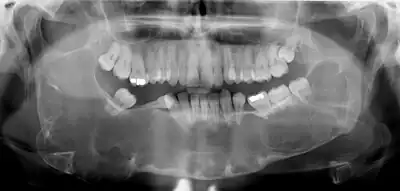

Radiograficamente, exibem uma área radiolúcida, apresenta-se como uma rarefação óssea uni ou multiocular, com bordas escleróticas frequentemente bem definidas, podendo ou não estar associadas com um dente impactado e, geralmente essa lesão possui uma discreta predileção de crescimento anteroposterior. Geralmente são analisadas radiografias panorâmicas e tomografia computadorizada, pois a radiografia panorâmica fornece, com qualidade, a extensão da lesão cística e sua relação com estruturas adjacentes, no entanto a tomografia computadorizada tem indicação indispensável para o planejamento cirúrgico, apresentando detalhes preciosos sobre a expansão da lesão, a localização de dentes envolvidos e a topografia de suas margens (espessura e perfuração das corticais ósseas)do que as radiografias convencionais. O uso racional indica tomografias computadorizadas somente para lesões extensas. O CO, pode muitas vezes ser confundido com cisto dentígero por em 44% dos casos está associado com dentes inclusos, porém observa-se também menos comum que o radicular, reabsorção óssea das raízes dos dentes adjacentes, normalmente ocorre um deslocamento do dente e não reabsorção da raiz. É importante salientar que apenas o diagnóstico histopatológico é determinante.